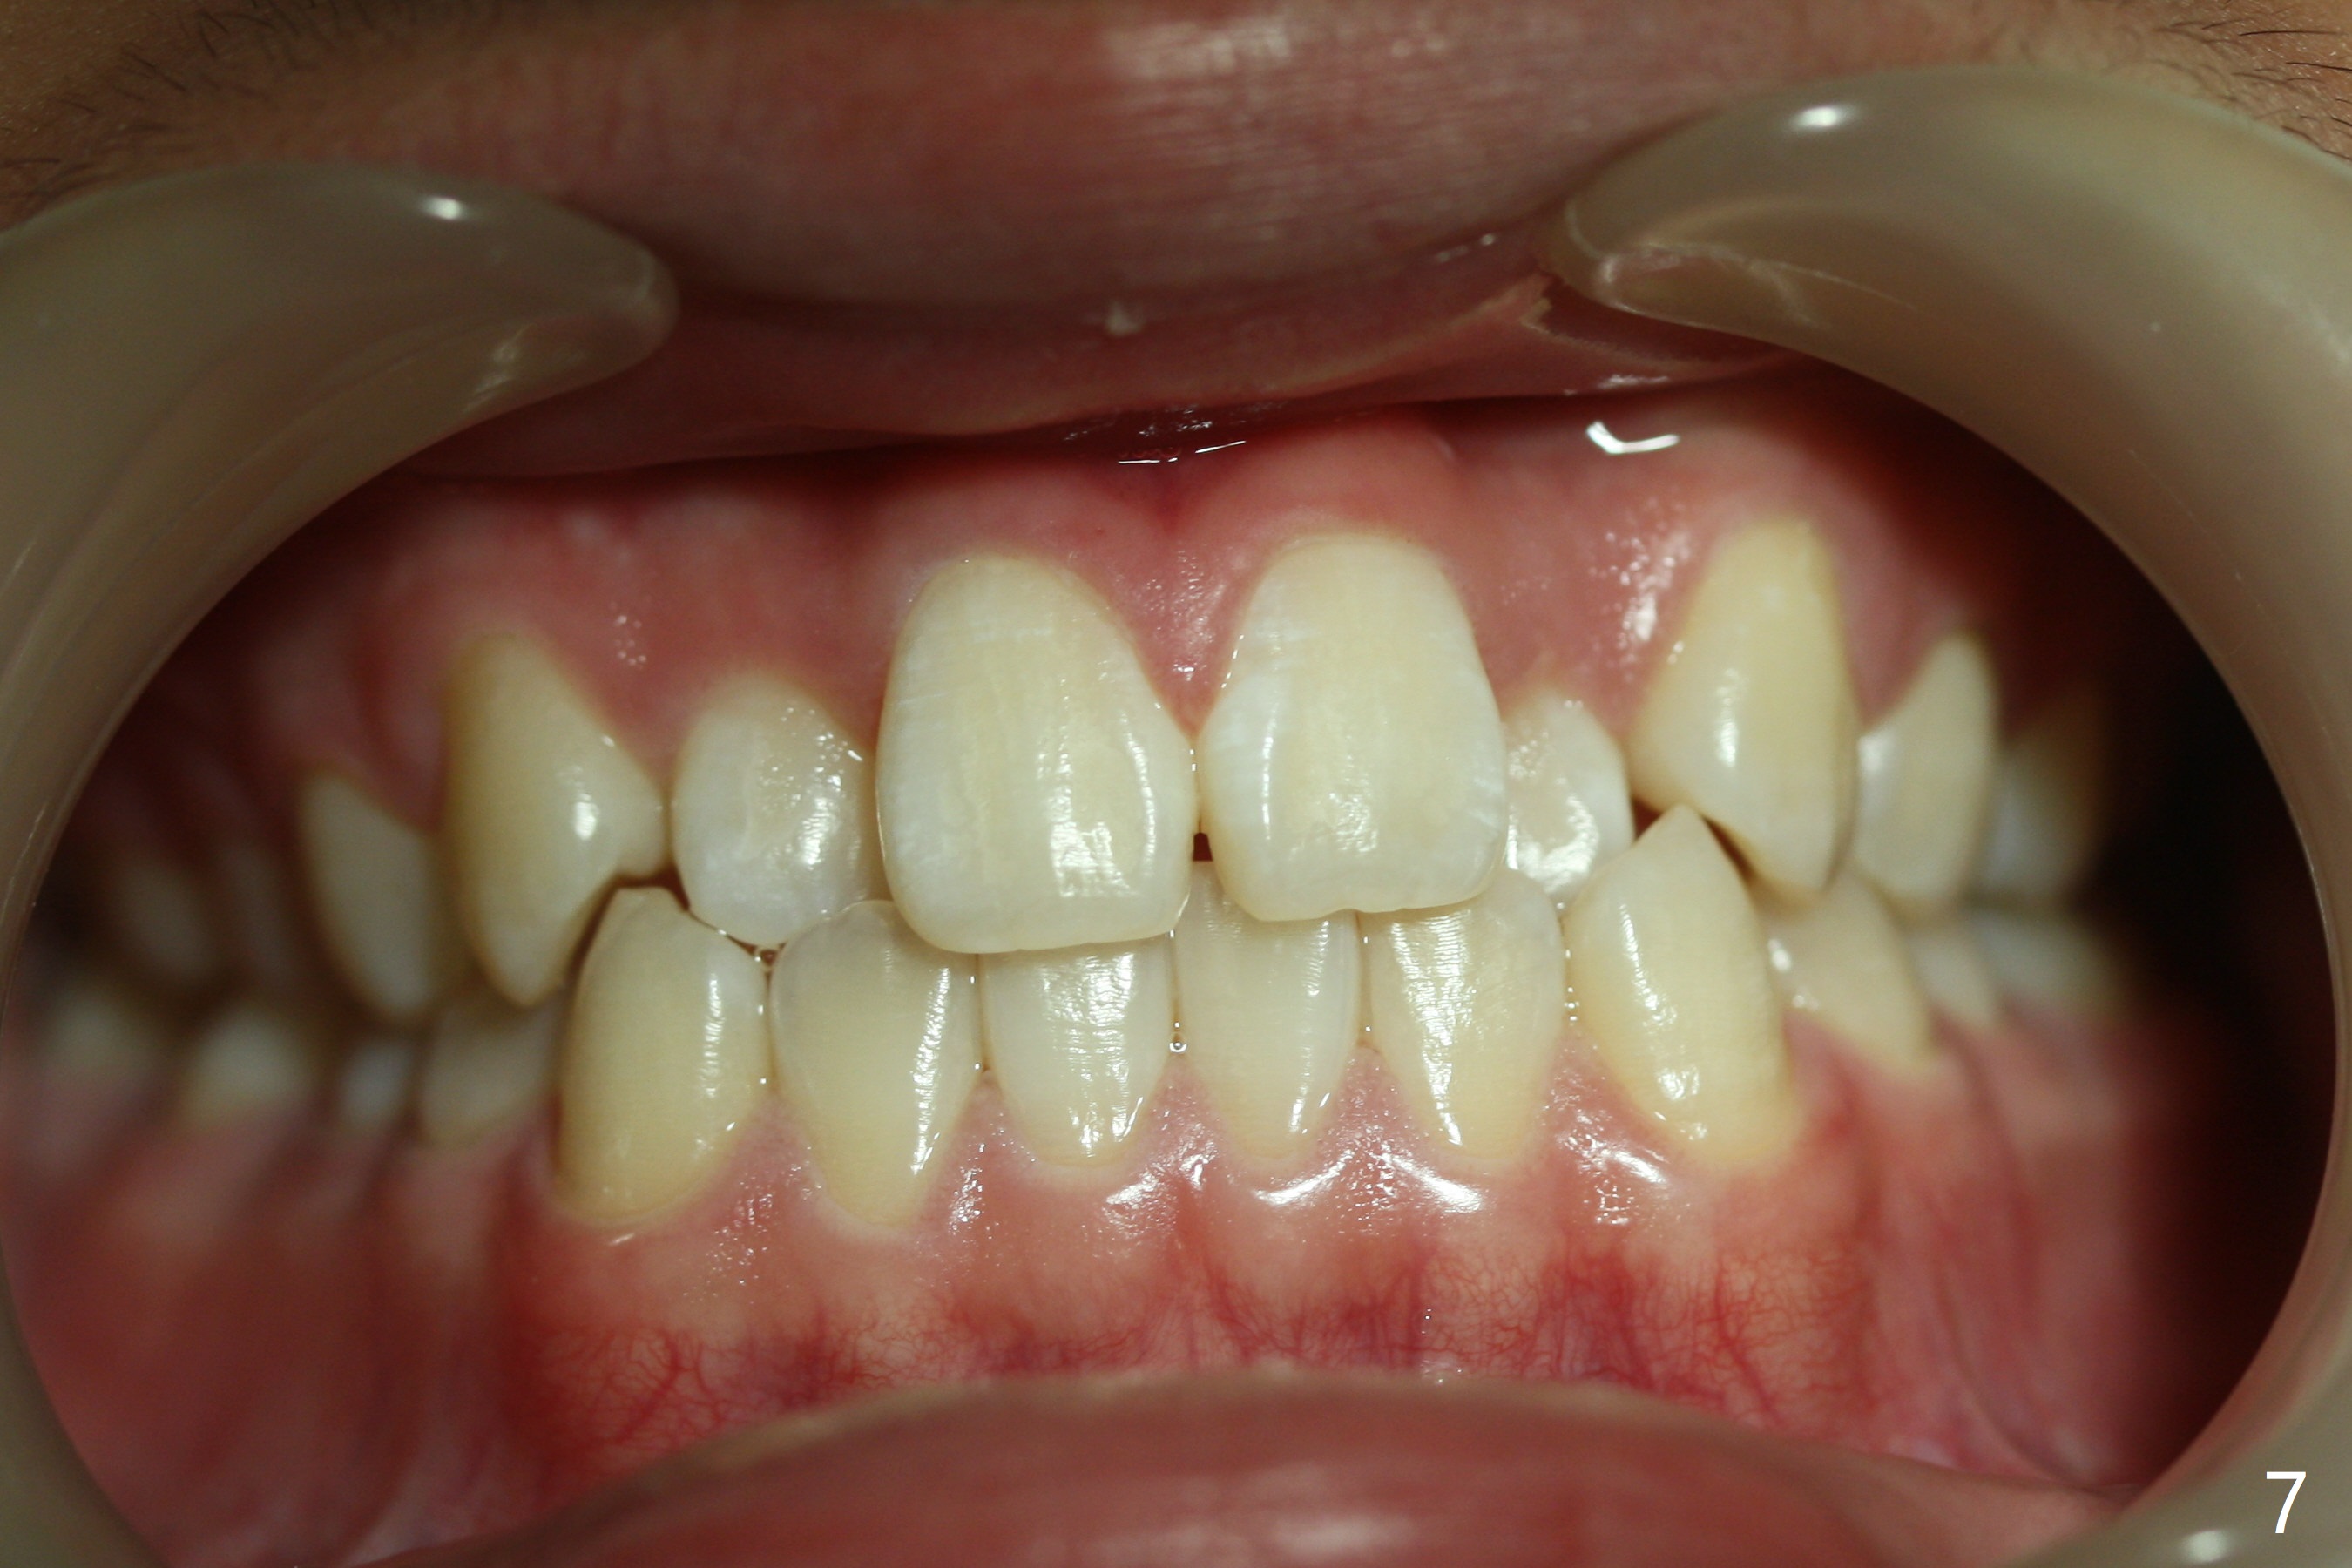

The upper dental midline of a 14-year-old man deviates the left (Fig.1,2,8) with midfacial concavity (Fig.3,4). The upper lateral incisors have cross bite, more severe on the left (Fig.6-8). Can we use open coil spring on the left first, a few months before the right, more or less to help correct the upper midline deviation? Cephalometric analysis shows Class III skeletal relationship (Fig.5,5',11).